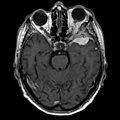

| Radiology | extra-axial, intradural lesion, dural tail sign (on MRI) |

Gross/Radiology

- Extra-axial, intradural.

- Can be extradural - very rare.[10]

- Dural tail sign (DTS) on MRI.[11][12]

- +/-Hyperostosis.

- Associated with invasion into the skull in ~20% of cases.[15]